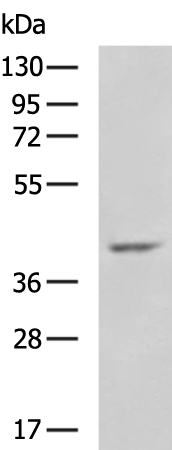

分类: 科研抗体货号: P08746别名: FP; PGL5; SDH1; SDH2; SDHF; CMD1GG应用: WB,IHC反应种属: Human, Mouse, Rat